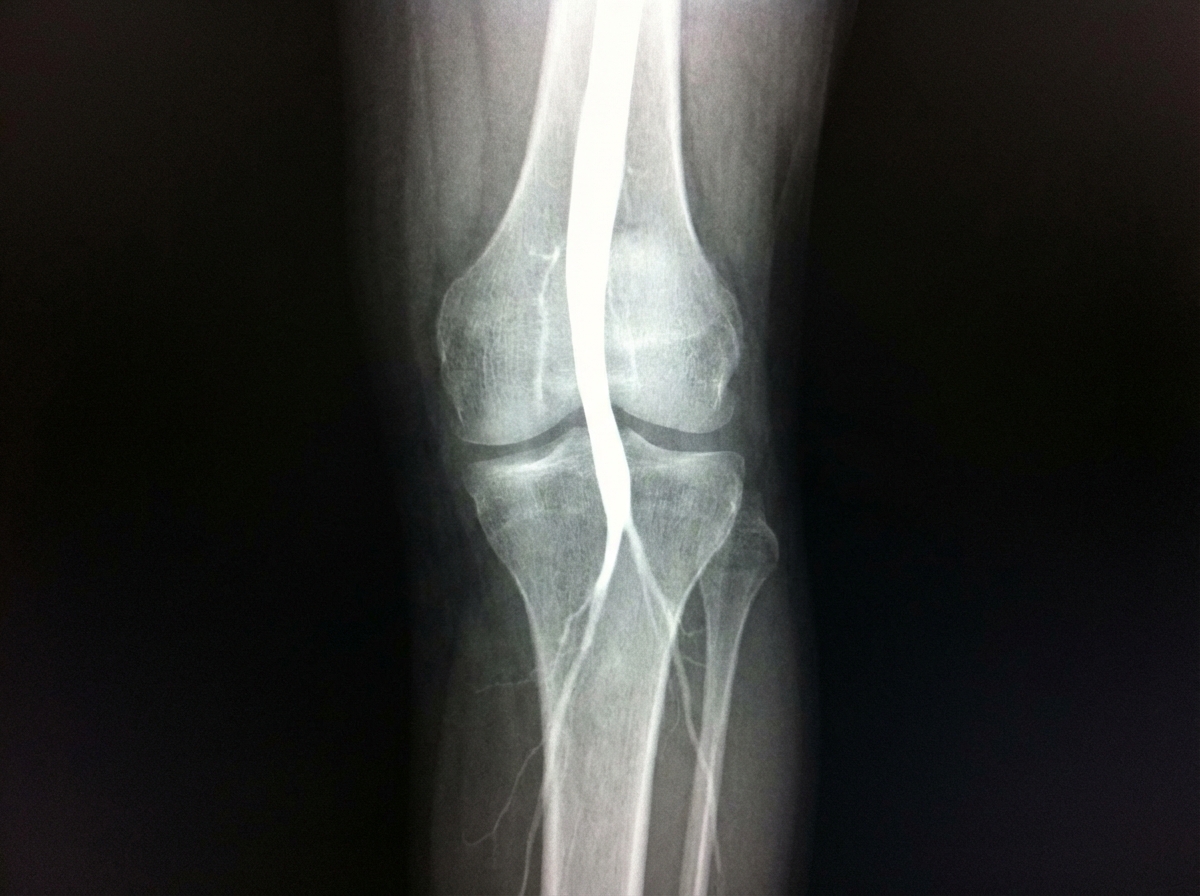

An HIV positive woman on ART was prescribed ergotamine for a migraine attack 4 days back. She presented with complaints that she is unable to feel her legs from the mid - thigh to her toes, for the past two days. The angiography image is given below. What is the likely diagnosis?